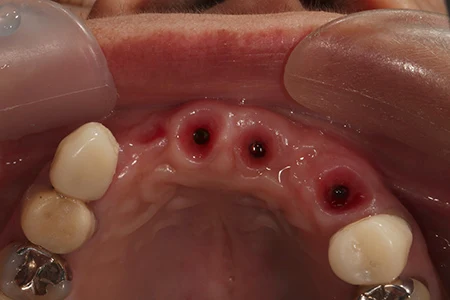

術前の状態。もともと前歯4本がなく、ブリッジが入っていたがブリッジを支えていた右上の犬歯が歯根破折のため抜歯となり、インプラント治療を希望されました。

移植した骨が生着するまで6ヶ月待った後、インプラントの埋入を行います。

インプラント埋入から2ヶ月後、仮歯を装着します。